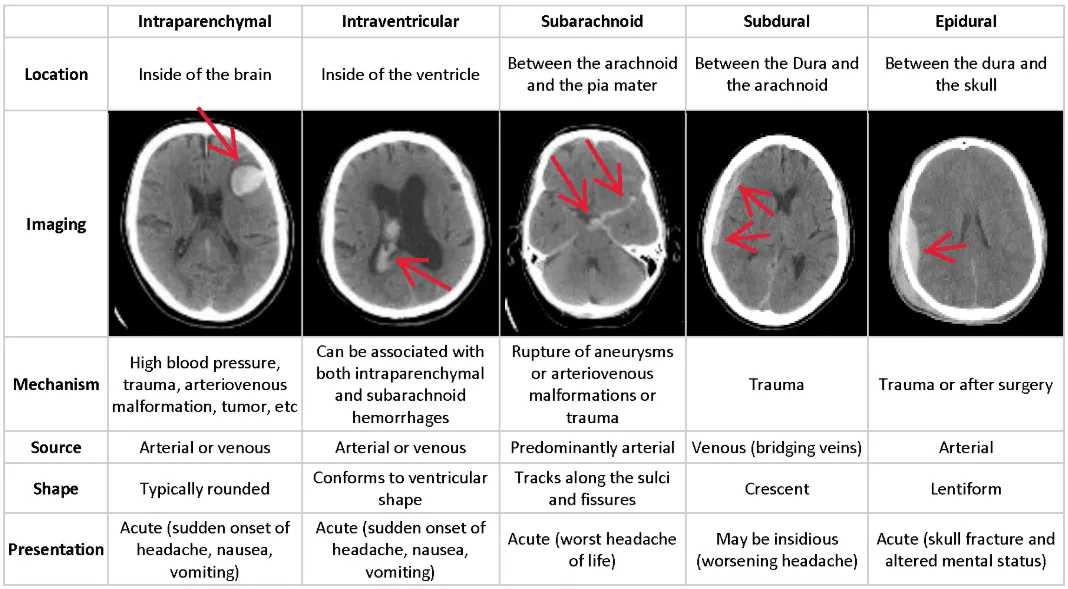

| Type | Vessel / Cause | Key Associations | CT Appearance |

|---|---|---|---|

| Epidural | Middle Meningeal Artery | Pterion fracture, Lucid interval | Lens-shaped (Biconvex) Stops at sutures |

| Subdural | Bridging Veins | Elderly, Alcoholics, Shaken Baby | Crescent-shaped Crosses sutures |

| Subarachnoid | Berry Aneurysm / AVM | ”Thunderclap” headache, Meningeal signs | Blood in Sulci LP: Xanthochromia |

| Intraparenchymal | Charcot-Bouchard (HTN) | HTN, Amyloid angiopathy, Basal Ganglia | Focal hyperdensity within brain |

| Intraventricular | Germinal Matrix | Premature infants (<32 wks) | Blood inside Ventricles |